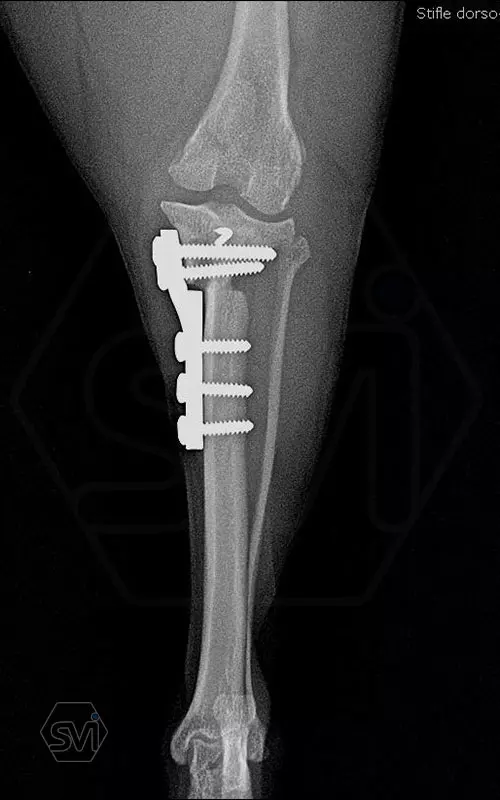

Introducing the TPLO-M „terraced” plate family from Smartvetimplants.com

In small dogs, medial patella luxation (MPL) and the rupture of anterior cruciate ligament (RACL) often occur simultaneously. During the surgical procedure, the joint must be stabilized and the patella fixed in the middle axis at the same time.

The solution of Smatvetimplants is the TPLO-M plate family with terrace:

Small TPLO-M plate:

part of a polyaxial locking system, symmetrical, available with 2.5 and 4.0mm terraces, torx-head, 2.4mm locking screws (2.0 and 2.4mm AO screws can also be inserted), material steel. Optimized for R12 and R15 blades.

Between October 2020 and December 2021, we performed 19 TPLO-M surgeries at the Animal Hospital in Nyíregyháza,: 16 times used the mini (2.0 R12) and 3 times the small (2,4 R15) TPLO-M plate.

The experience is very encouraging, we find the system and plates suitable for the simultaneous treatment of MPL and RACL. ( in case of 4/4 pat. lux. also). We will back soon with details.